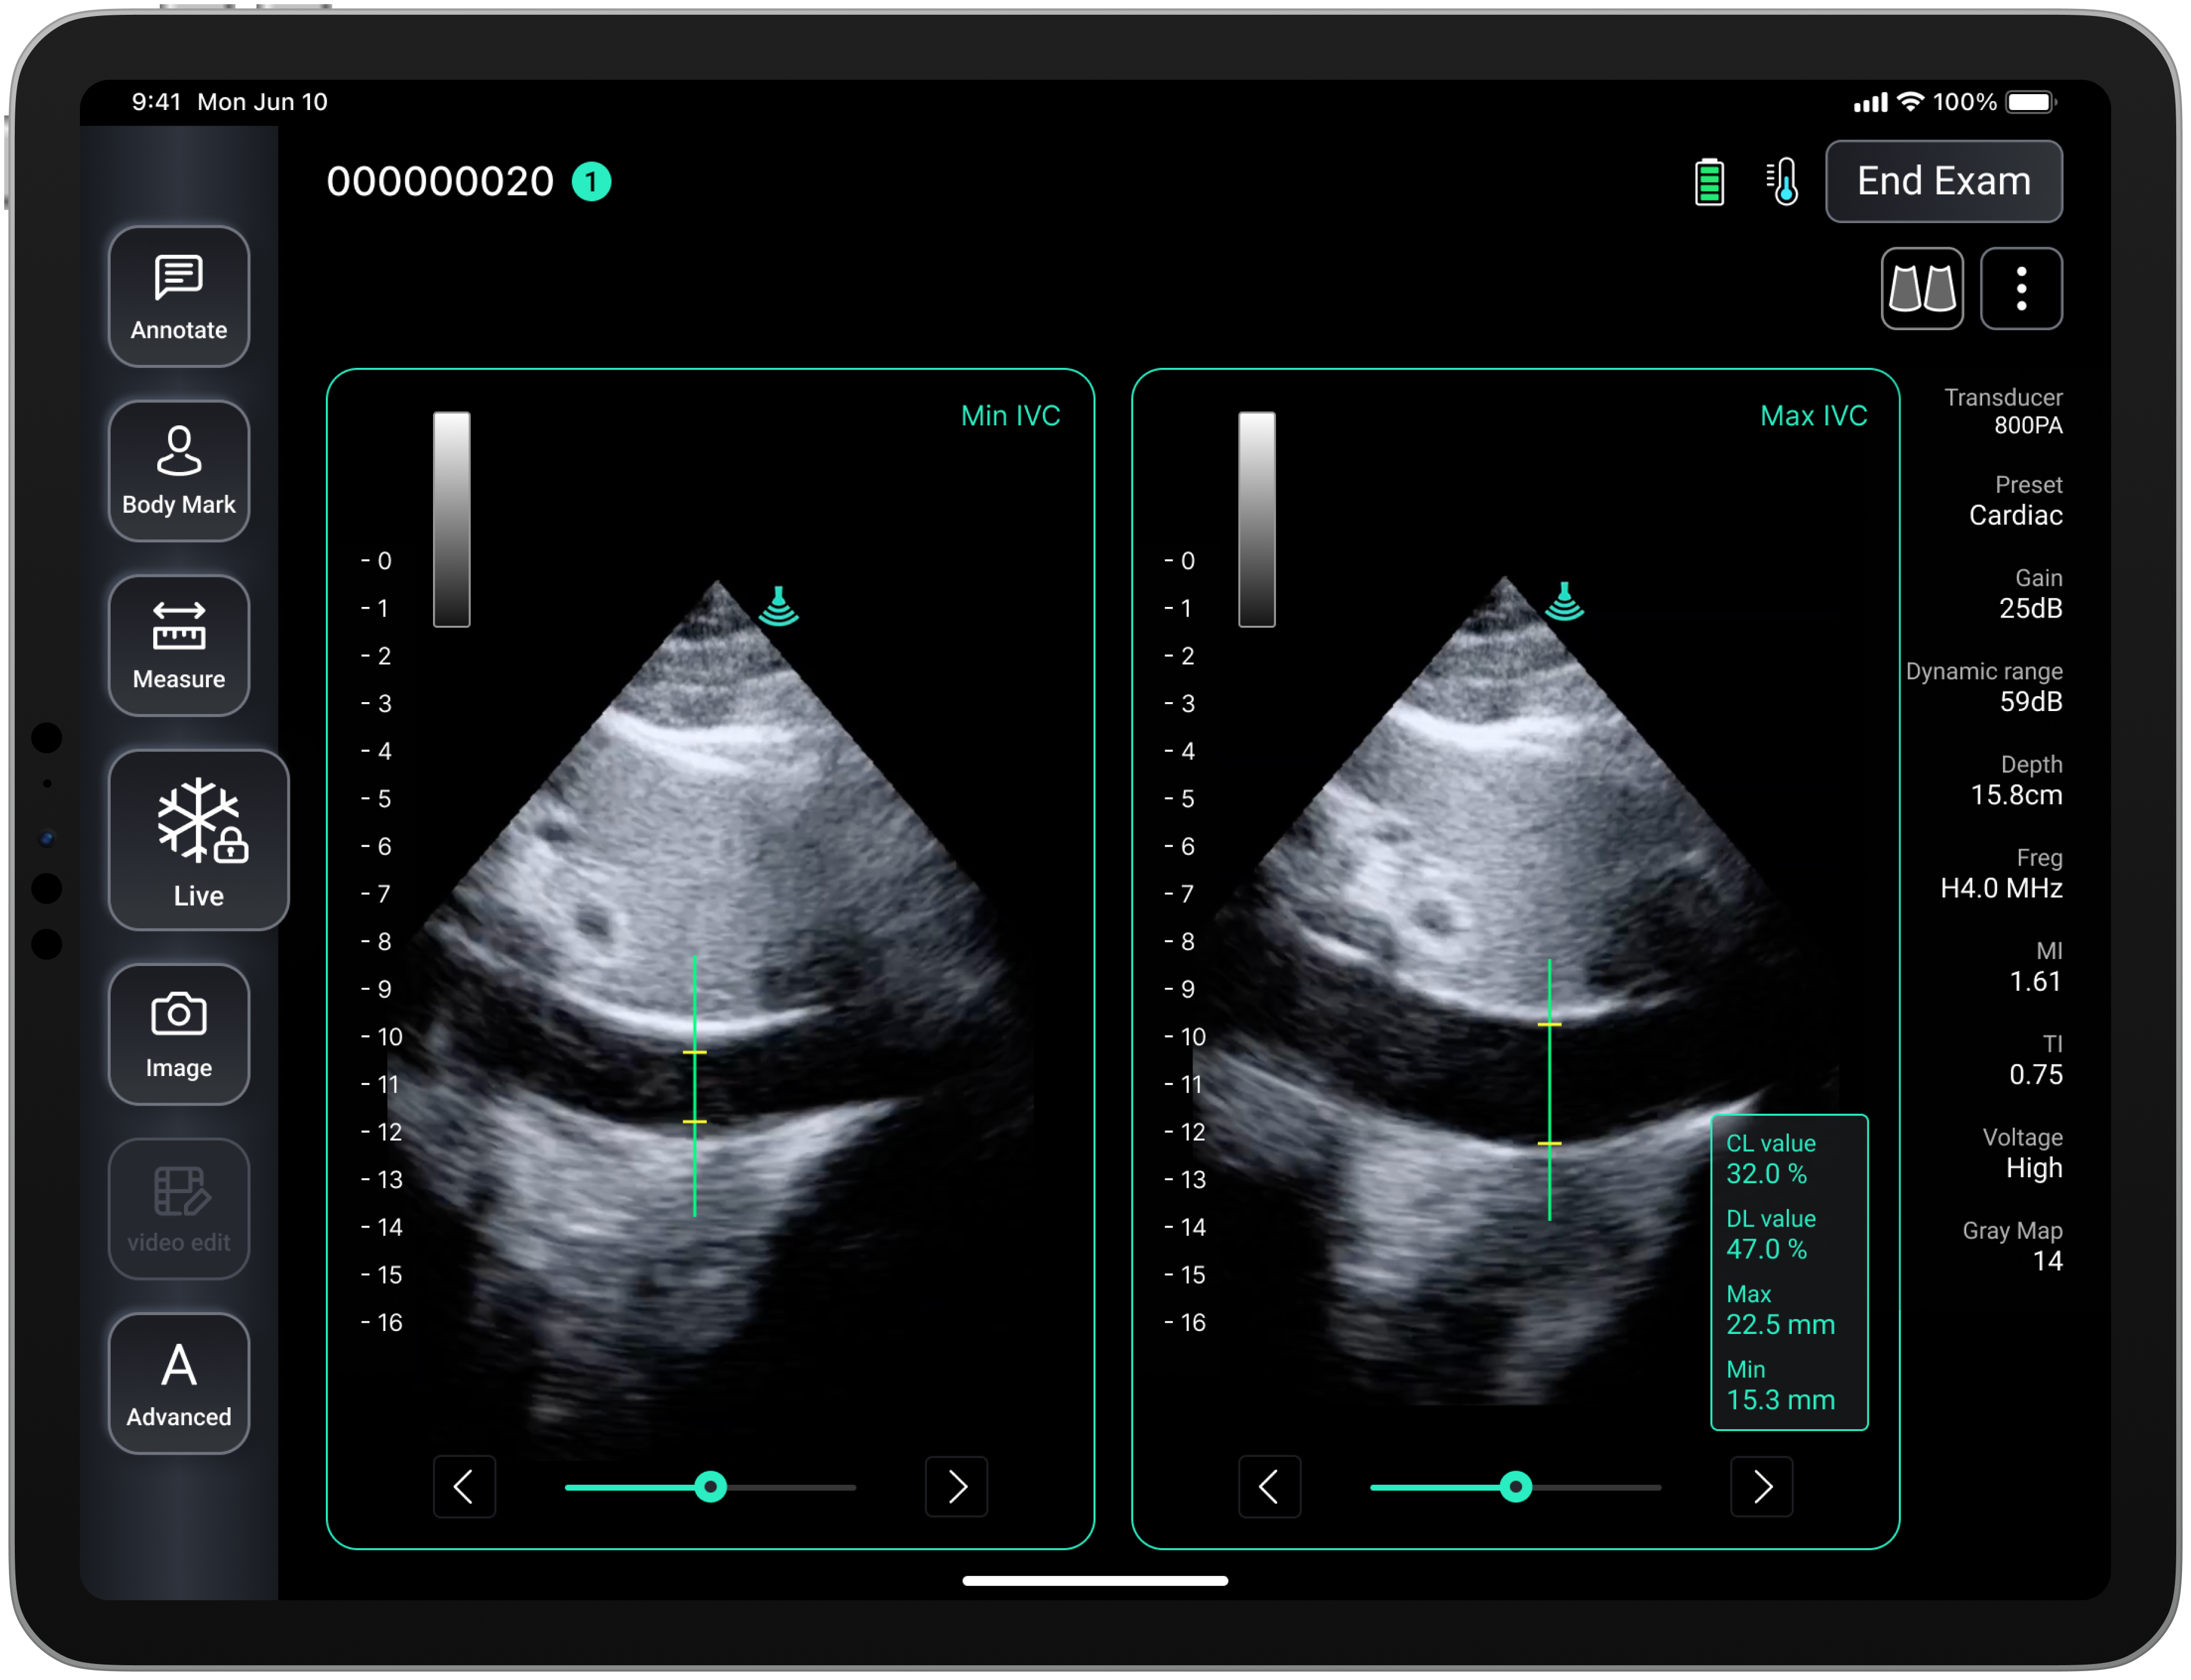

Auto IVC: Fluid Assessment for Emergency Care

The Auto IVC feature is designed to automatically detect and measure the diameter and collapsibility index of the inferior vena cava (IVC). This noninvasive tool provides critical insights into a patient’s volume status, enabling clinicians to quickly evaluate fluid responsiveness in cases of shock, hypotension, or unstable hemodynamic states.

The ability to assess fluid status is particularly vital in emergency rooms and intensive care units (ICUs). With Auto IVC, healthcare professionals can make rapid decisions regarding fluid resuscitation and management, potentially improving patient care and outcomes in critical situations.